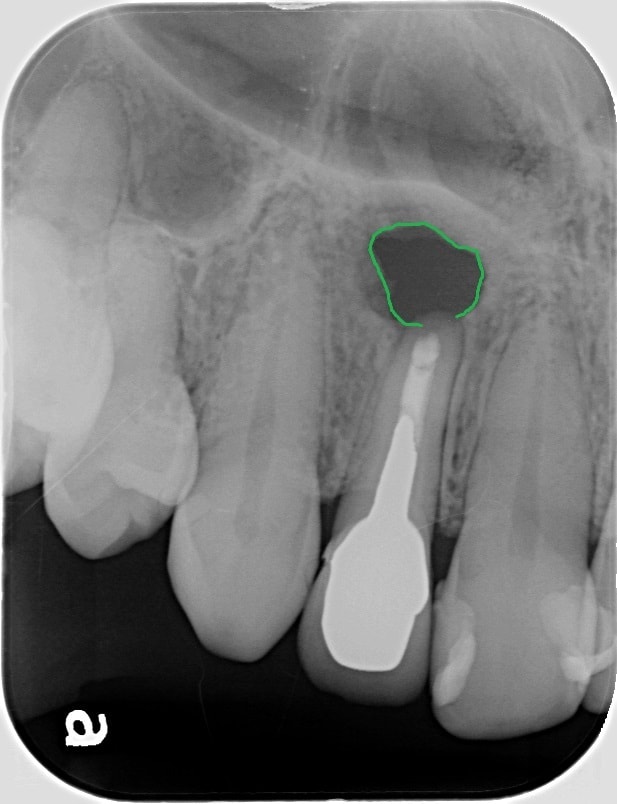

術後1年7ヶ月

様々なことを総合的に考えて、MTAセメントを用いて歯根端切除術という手術を行いました。

1年7ヶ月後のレントゲンで、緑の線で囲まれている部分が小さくなってきているのがわかると思います。歯の周りに骨が再生してきていると思われます。これから経過をしっかり追っていく必要はあるかと思いますが、取り合えず一安心です。

どんな治療も一発勝負ですが、特に、歯を残せるか残せないかの瀬戸際の治療の経過がいい方向に向かうとホッとします。

インプラントや入れ歯、ブリッジなど様々な治療法が存在しますが、やはり自分の歯に勝るものはないので、出来るだけ歯が保存できるような方向で治療を行っていけたらと思います。治療後の状態を把握するためにも、衛生士やドクターによる定期的なメンテナンスは欠かすことはできません。

治療が終わったら終わりではなく、その状態をできるだけ長期に維持するために、これから始まると思っていただけると幸いです。